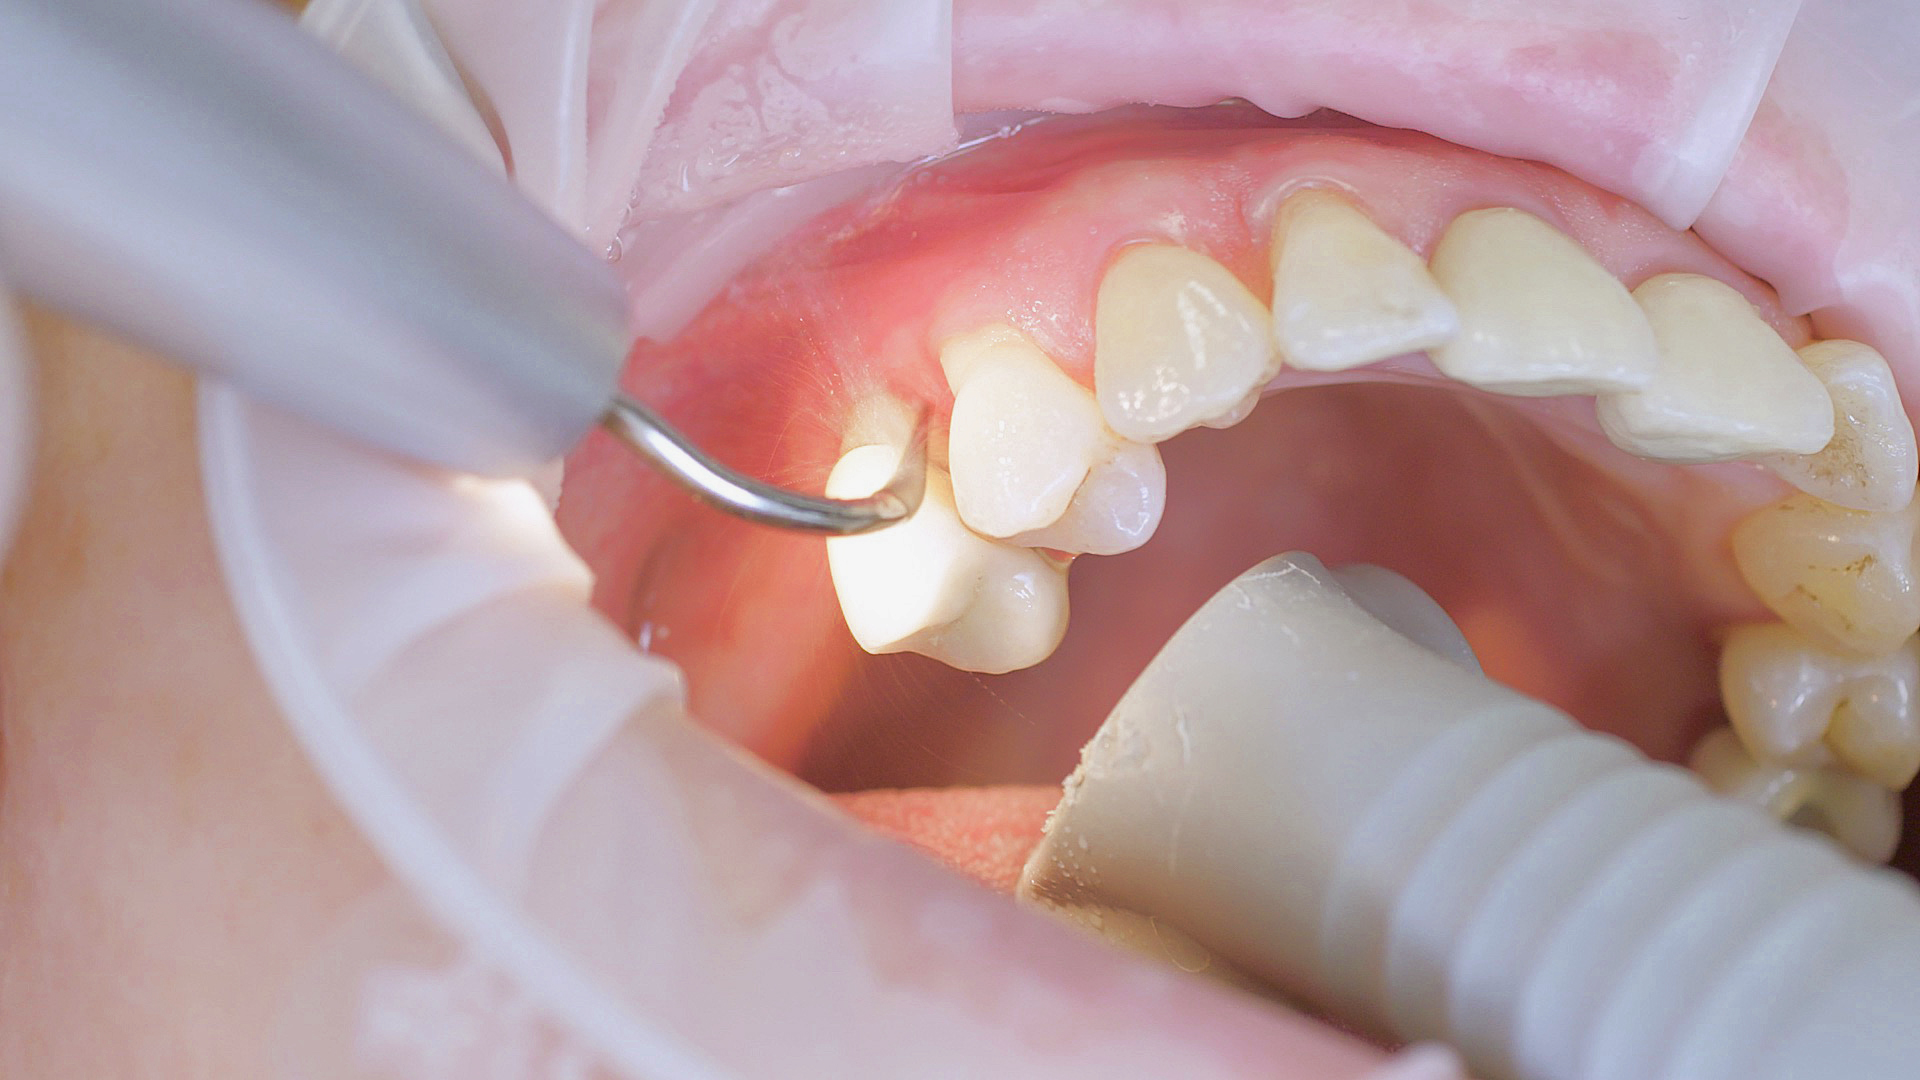

Removal of subgingival coatings (debridement) is carried out using sonic or ultrasonic devices and special periodontal tips as initial periodontal treatment (Fig. 3). Manual instruments can also be used. Further surgical and/or regenerative measures may be necessary, depending on the situation.

Sonar technology, W&H Proxeo with 1AP tip

Fig. 3: If marginal periodontitis is diagnosed, the initial debridement can be carried out very efficiently with an air scaler (sonar technology, W&H Proxeo with 1AP tip)